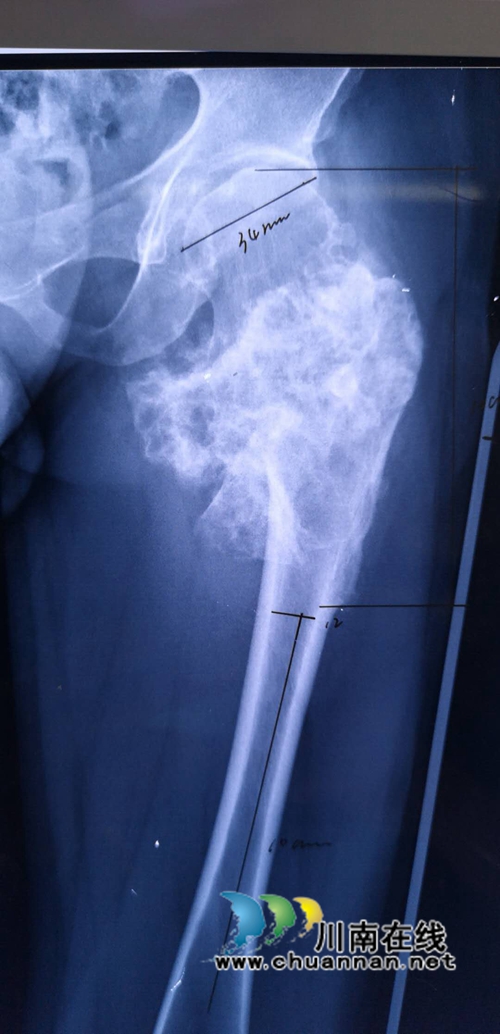

患者男性,29岁,三年前曾因左股骨近段包块在其他医院进行了包块切除术。但是术后一年左右包块就复发,复发后导致患者局部出现阵痛阵痛,且走路也出现跛行。在经我院检查诊断后,最终确诊为左股骨上段软骨肉瘤(高恶性)。

如果按照以往手术方式为肢体切除,但是考虑到患者年轻,截肢对患者心理、生活影响较大。在经过与患者沟通和我院骨科集体会诊讨论后,由张戈副主任医生主刀行瘤段切除及肿瘤假体置换治疗。

该手术难度较大,但可保留患者肢体及功能。经四个多小时的努力,成功为患者实施手术。